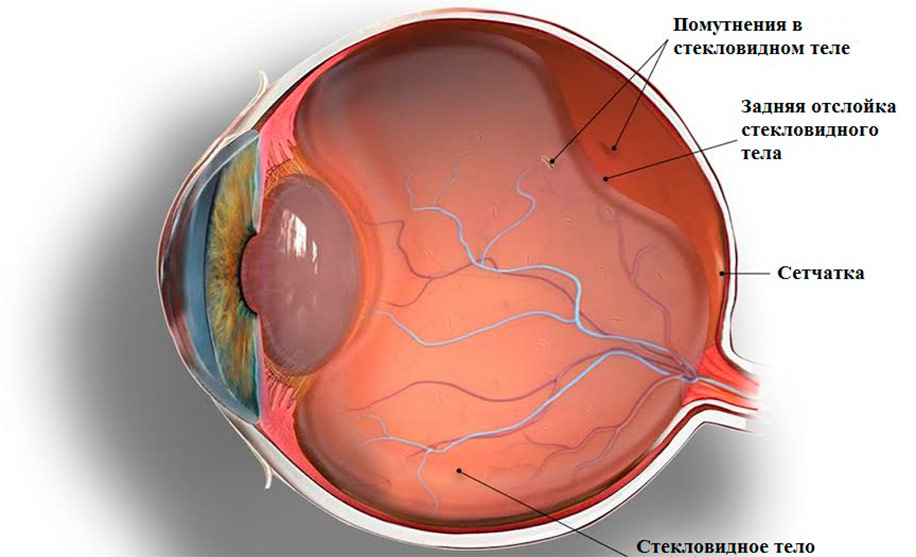

Изображения и анатомия сетчатки глаза

Раздел: Визуальный дайджест